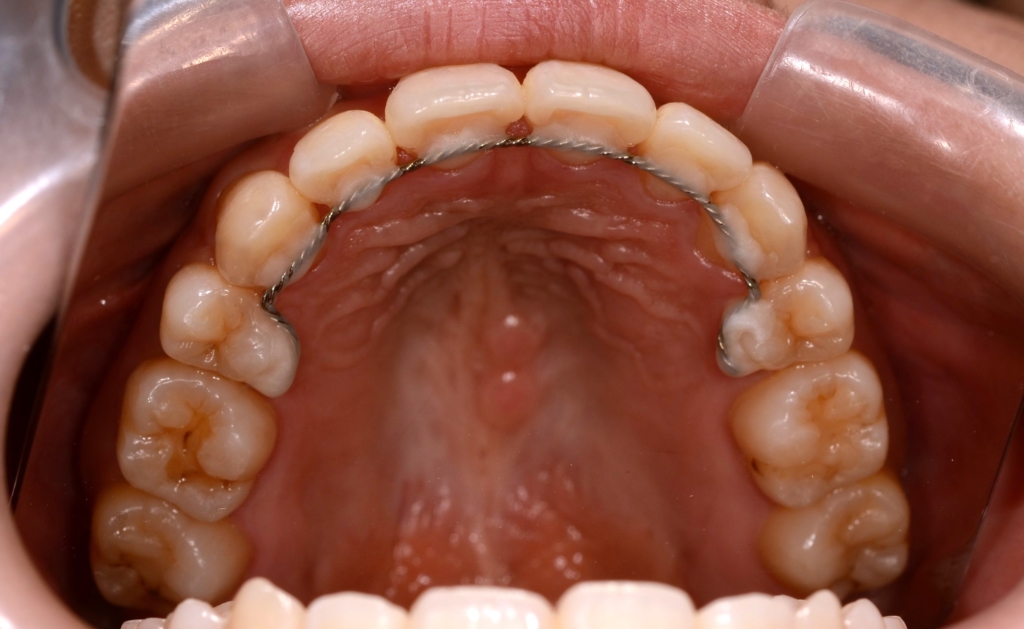

ついでに、歯並びの比較です

上段が矯正治療前、下段が矯正治療後